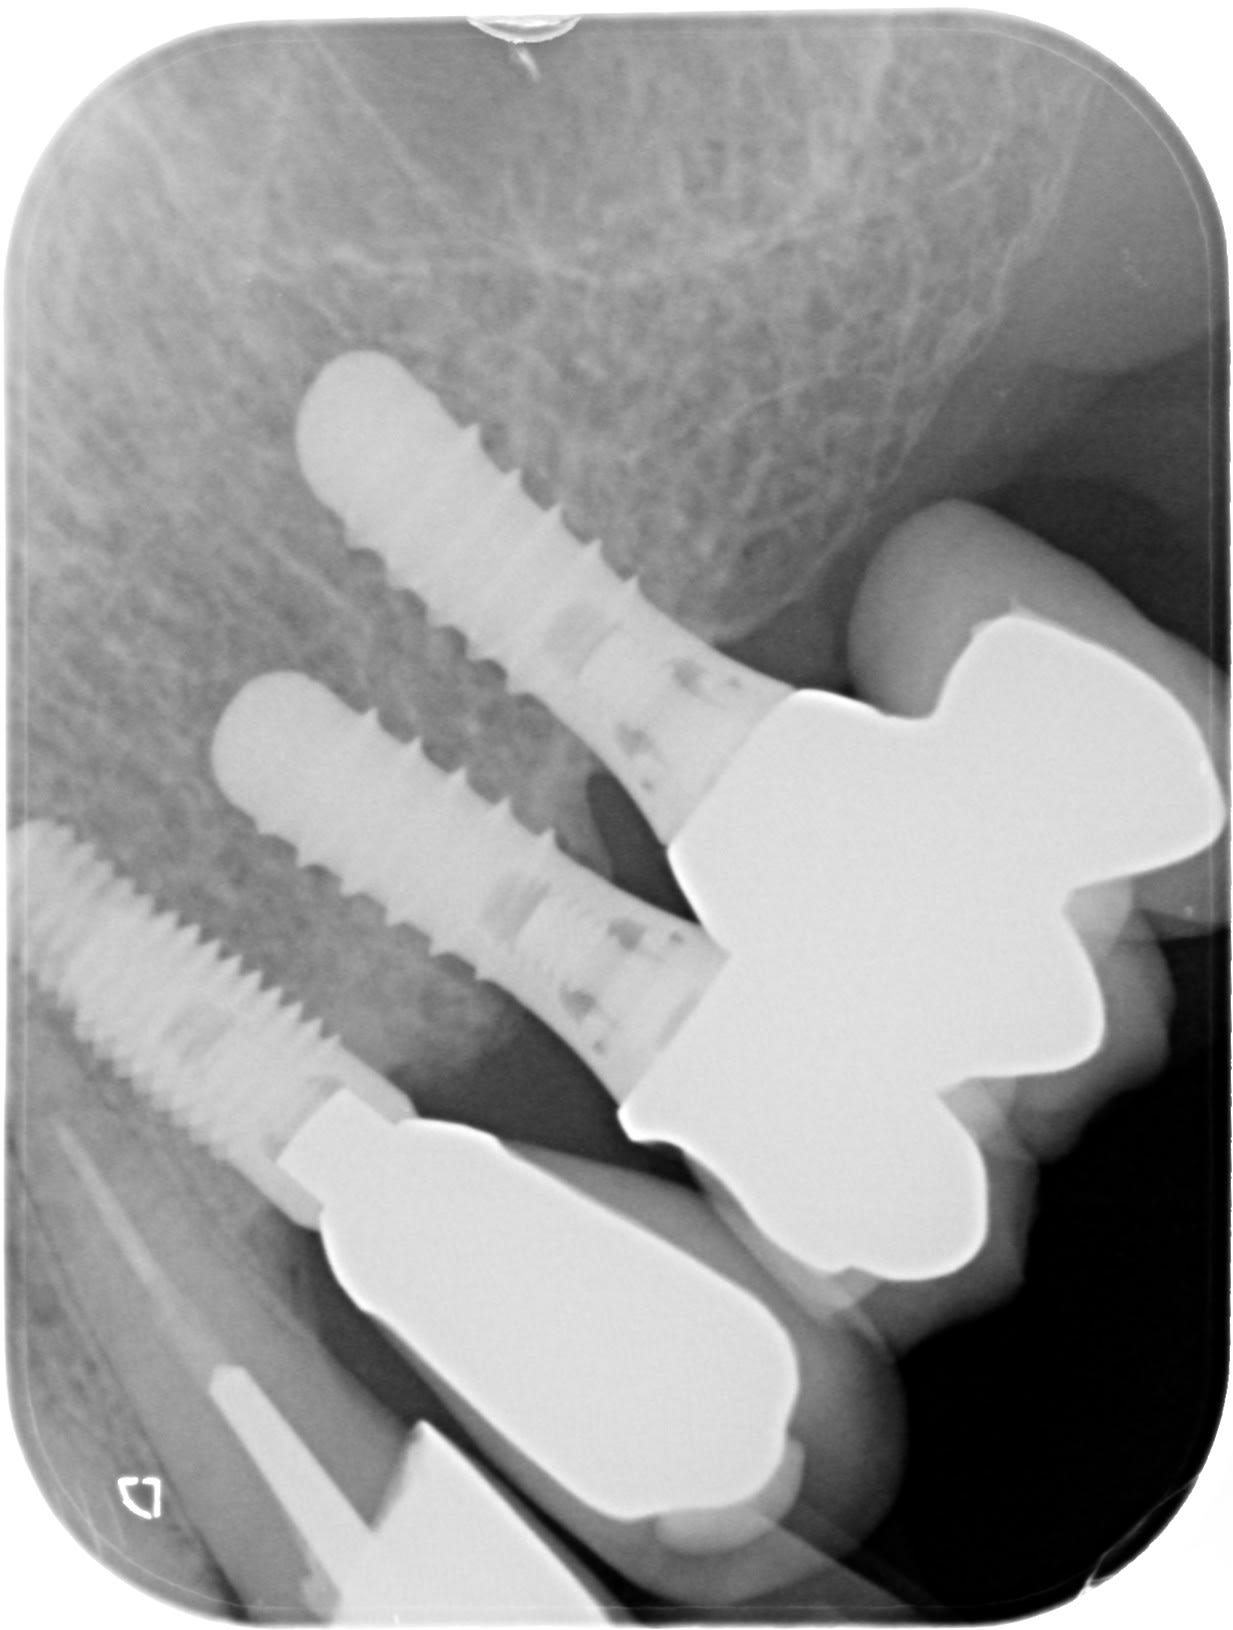

implant posé il y a au moins 10 ans - aucune idée de l'origine (Suisse ou france) ni du poseur, concernant la 23

Couronne implantaire mobile . soit casse vis soit vis desserrée ?

dans tous les cas, quel implant selon vous, afin de trouver le tournevis pour aller regarder ?

Impossible de mieux centrer la RX malheureusement

ça ressemble à un TSV Zimmer

parce que C'EST un TSV Zimmer

tournevis hex 1.25mm couple de serrage 30Ncm